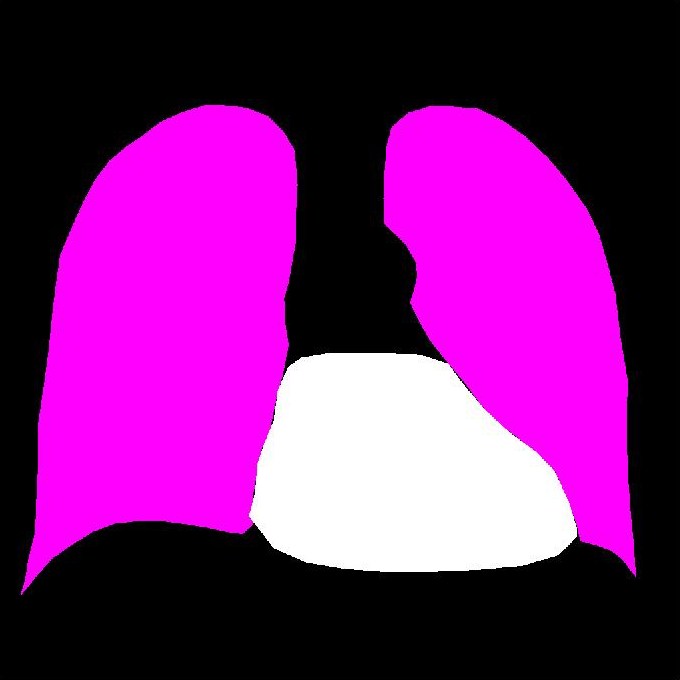

3.4 Localization Scheme

The sensitivity of softmax score to occlusion of a certain region in the chest X-Ray was used to find which region in the image is responsible for the classification decision. We followed the localization using occlusion sensitivity described in [25]. In this experiment, a patch of square size is occluded in the CXRs and is observed whether the classifier can detect pathology in the presence of the occlusion. If the region corresponding pathology is occluded then the classifier should no longer detect the pathology with higher probability and thus this drop in probability indicates that the pathology is located at the location of the occlusion. This occluded region is slid through the whole CXR and thus a probability map of the pathology corresponding to the CXR is obtained. The regions where the probabilities are below a certain threshold indicates that the pathology is likely to be occupying that region. Thus, the pathology in the CXR can be localized.

The overall classification scheme and localization scheme is visualized in Fig. 2. In summary, the classification scheme (top) is ensemble of different types of DCNS and the localization (bottom) is obtained from the overlapping occlusions.